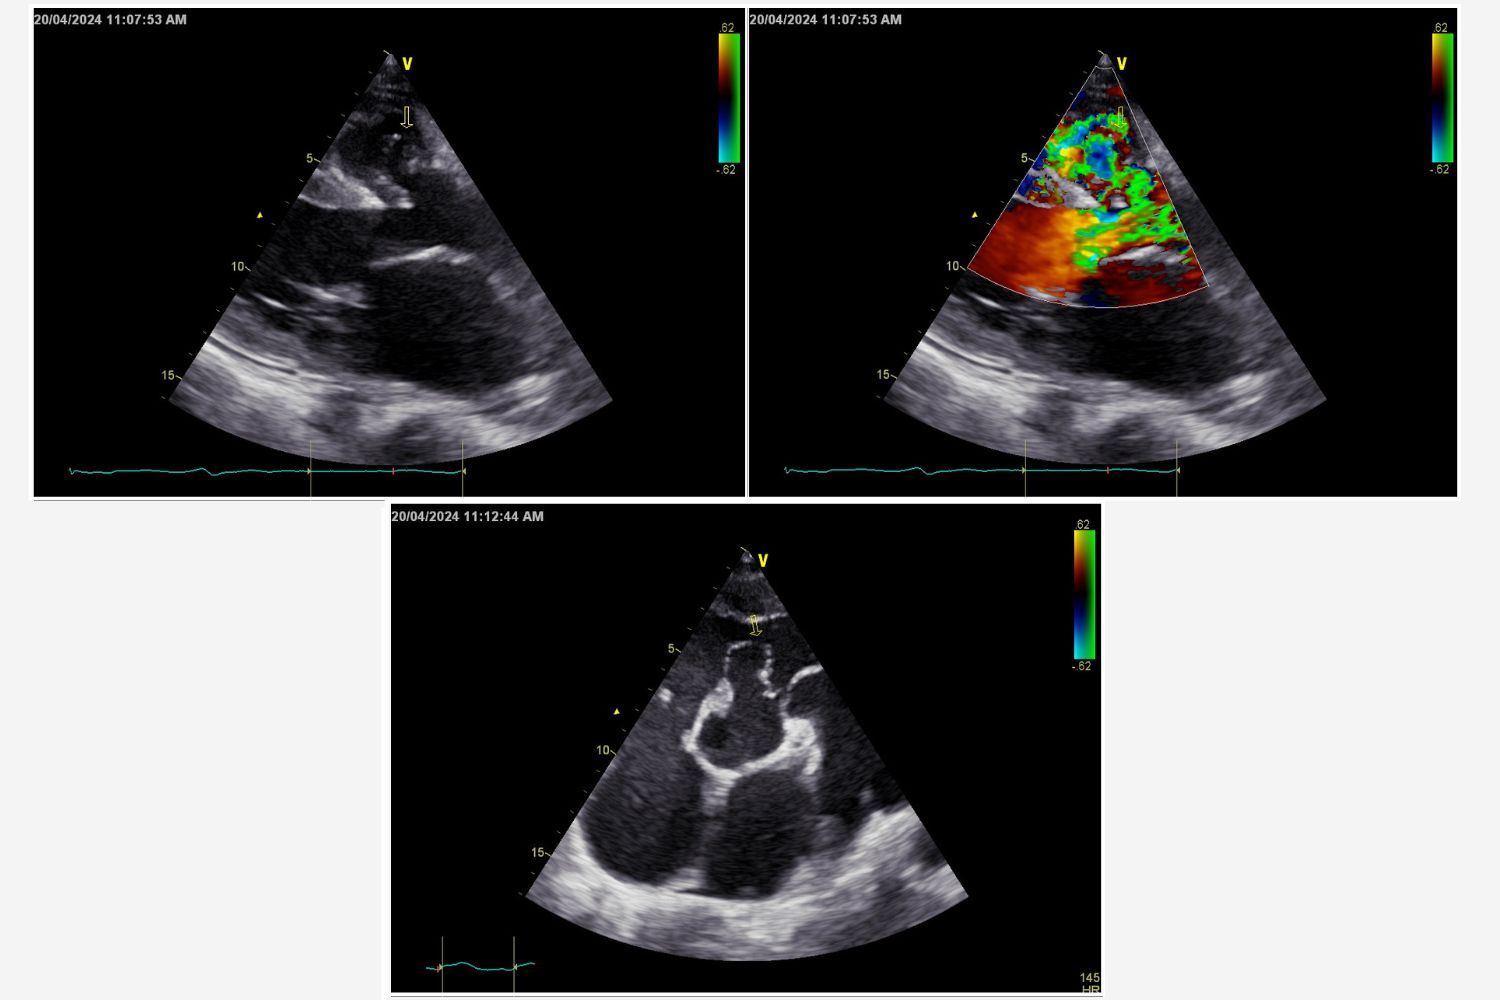

Image of the Week - 17 December 2025

Image of the week